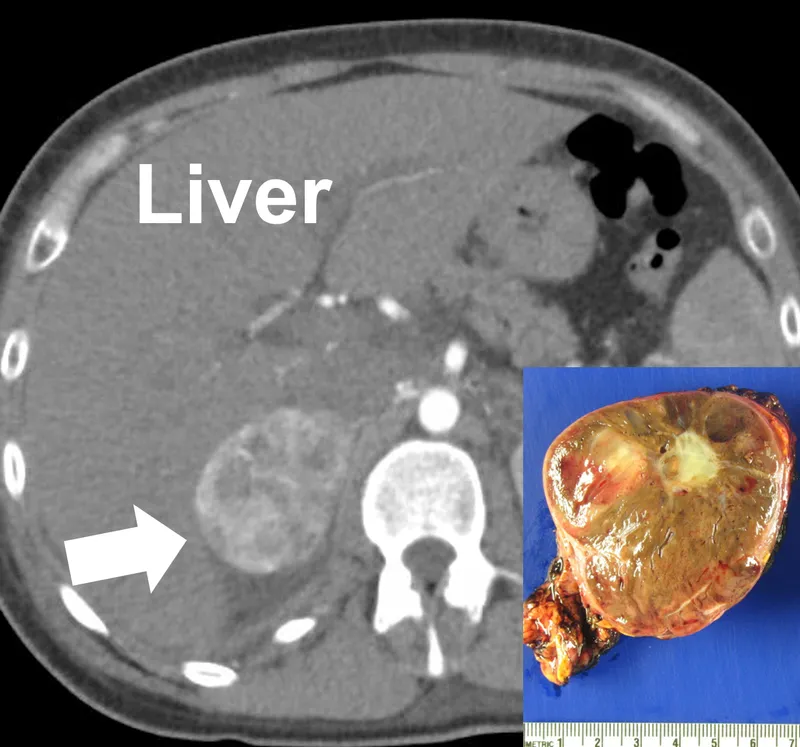

- Imaging (Post-Biochemical Confirmation):

- Anatomical: CT abdomen/pelvis (initial); MRI (children, pregnancy, contrast allergy).

- Functional: ¹²³I-MIBG scintigraphy; ⁶⁸Ga-DOTATATE PET/CT (metastatic/extra-adrenal disease).